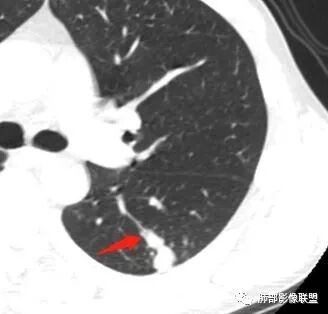

南边:问一个问题:支气管在这里堵了吗

Shelia:堵了,而且支气管壁增厚了。

Coke with ice:我认为堵了,不倾向于肿瘤的堵塞。对于这个病例来说,结核的爬行和肿瘤的堵塞鉴别点不清晰。

南边:这是支气管吗?

张立:是

南边:

远端有支气管显示,提示支气管局部没有堵塞,这个近端的看起来堵塞的支气管可能是假象。